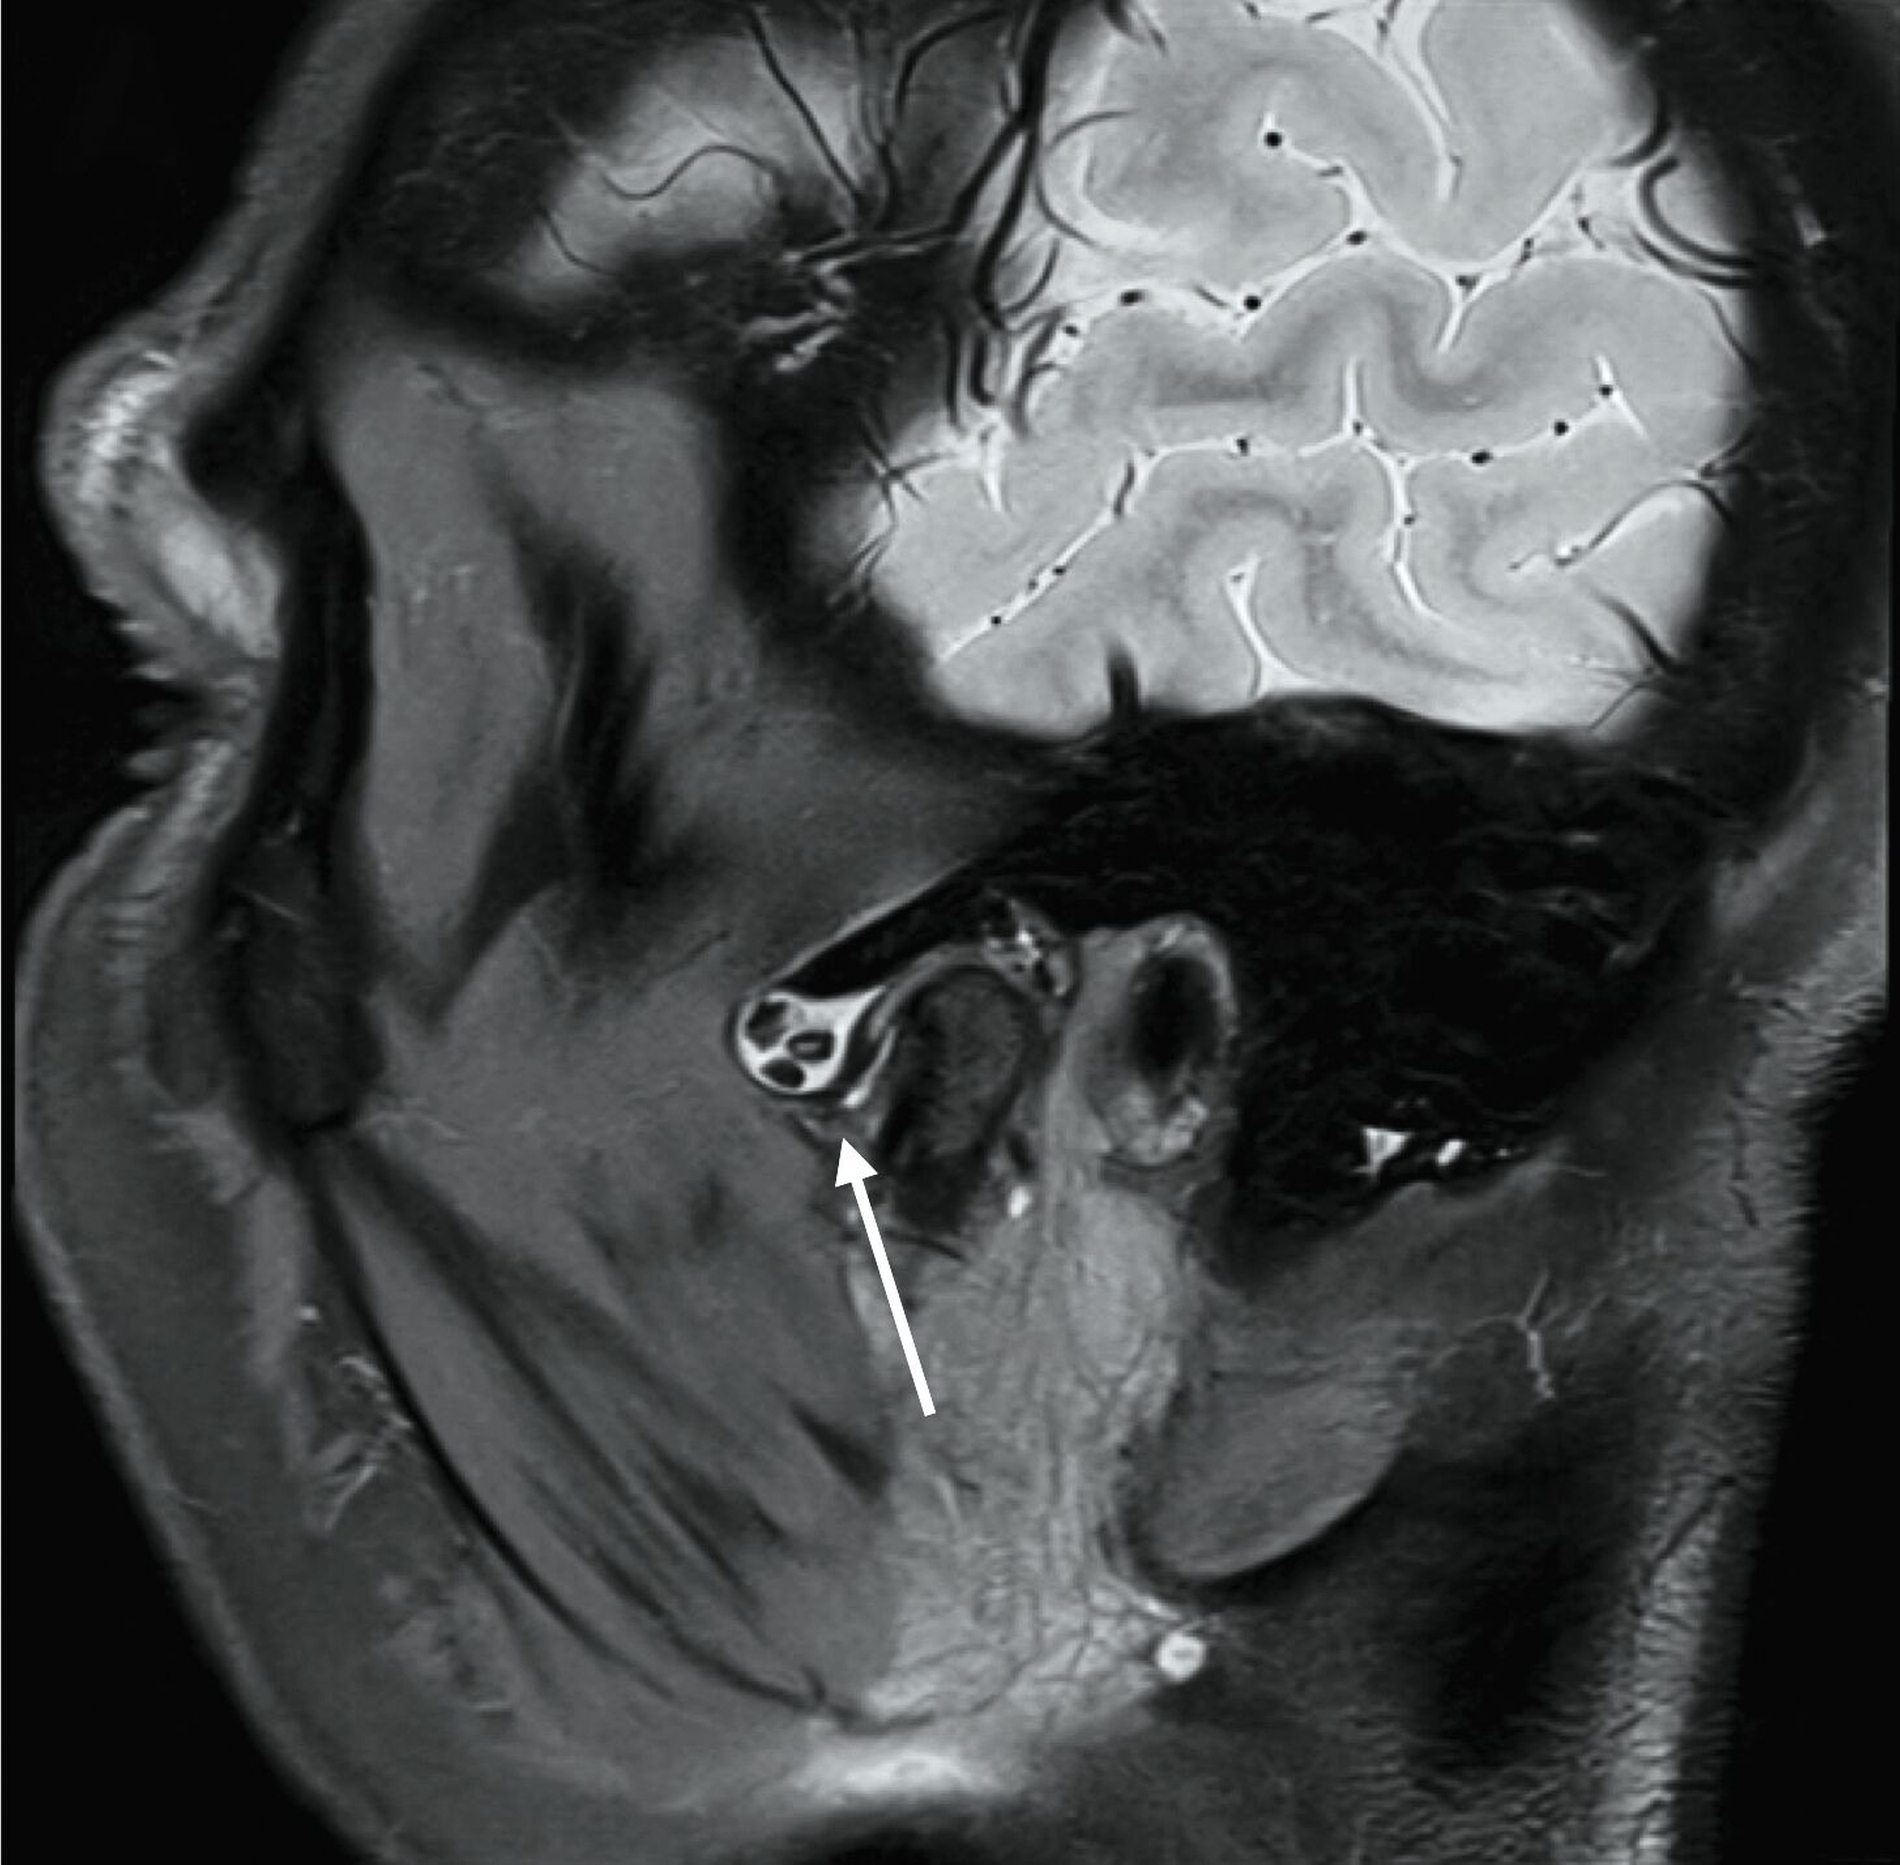

Eine 63-jährige Patientin stellte sich mit einem durch den Hauszahnarzt detektierten Zufallsbefund im linken Kiefergelenk vor. Aufgrund von Mundöffnungsstörungen hatte sie einen Monat zuvor dessen Praxis aufgesucht. Auf der in der Praxis angefertigten Panoramaschichtaufnahme (Abbildung 1) erkennt man opake, rundlich-strukturierte Raumforderungen über dem linken Kiefergelenk.

Die differenzialdiagnostische Abklärung erfolgt nach eingehender Anamnese und klinischer Untersuchung zunächst über die bildgebende Darstellung mittels Magnetresonanztomografie, da die nicht verkalkten Gelenkkörper in der Nativ-Computertomografie (und in der Digitalen Volumentomografie) nicht oder nur sehr spät nachweisbar sind. Die Panoramaschichtaufnahme ist gerade in frühen Phasen der Erkrankung häufig nicht zielführend. In späten Erkrankungsstadien können die Distraktion des Gelenkspalts oder die sekundäre Verkalkung auf das Vorhandensein der Gelenkkörper hinweisen [Reich und Neff, 2022].